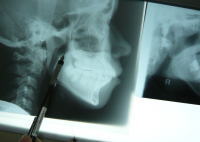

STEP 2 精密検査

レントゲン検査・写真撮影(口腔内・顔面)・歯型の採取等を実施します。これをもとに、治療の計画を立てていきます。